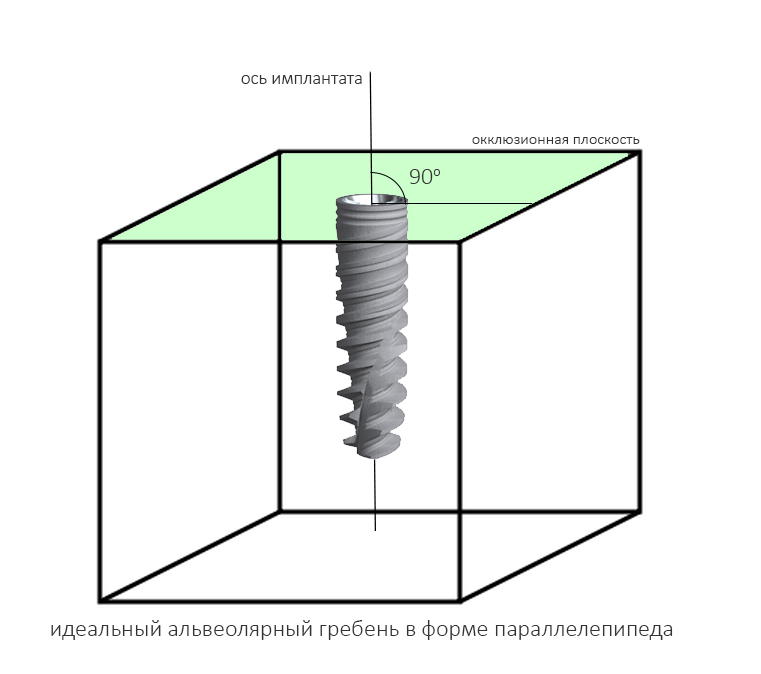

Гораздо менее понятная штука — это ангуляция имплантата, т. е. угол, образуемый осью импланта и акклюзионной плоскостью альвеолярного гребня.

Если бы челюстная кость имела бы правильную геометрическую форму (например, параллелепипеда), то не было бы нужды рассматривать ангуляцию — мы ставили все наши имплантаты под углом 90 градусов к окклюзионной плоскости, и было бы всем счастье:

Но в жизни всё сложнее.